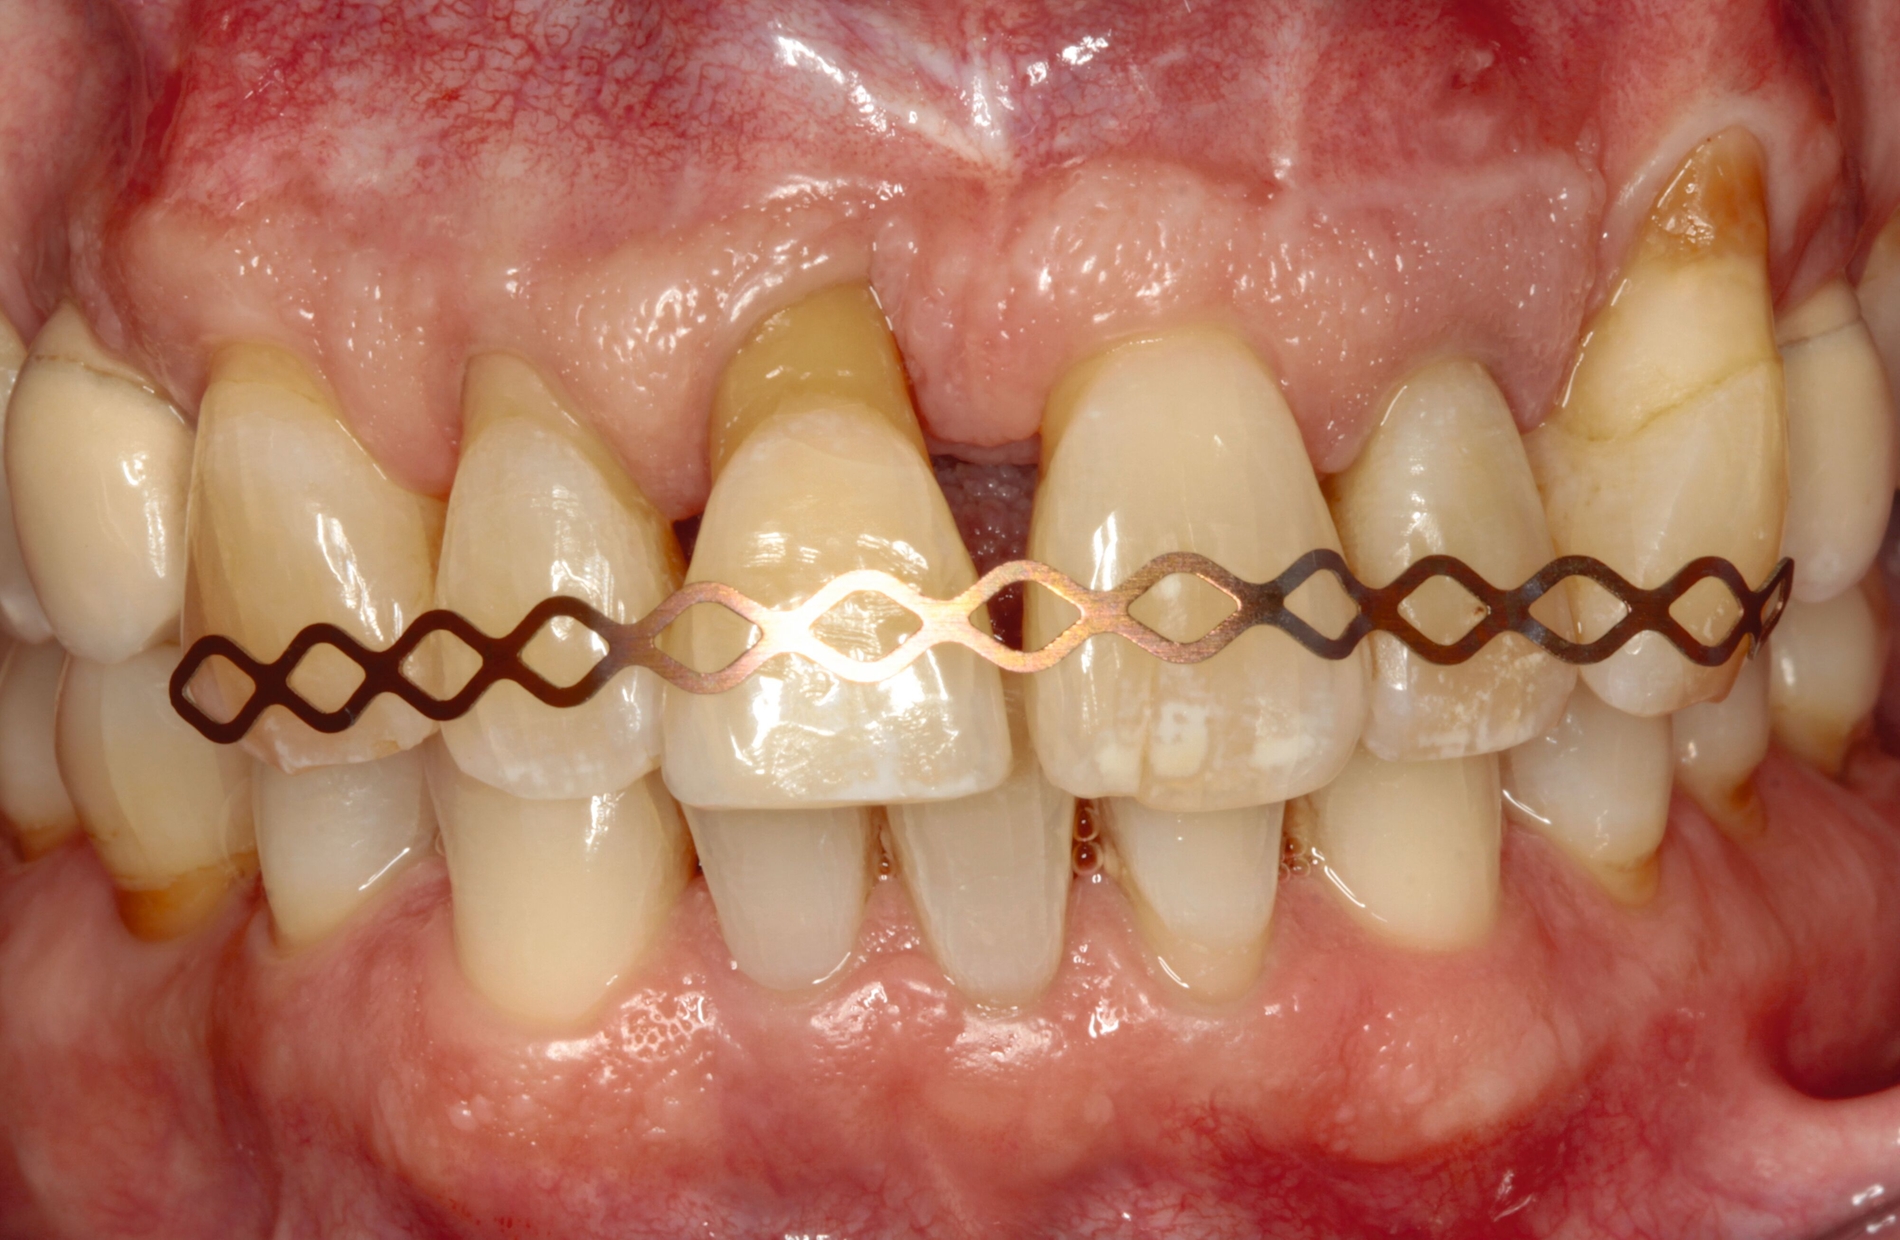

Entsprechend der hier aufgeführten schwachen wissenschaftlichen Evidenz lässt sich schlussfolgern, dass Zähne mit einem Lockerungsgrad II oder höher möglicherweise von einer Schienung vor regenerativen parodontalchirurgischen Eingriffen profitieren können [Cortellini et al., 2001]. Diskutiert wird in diesem Zusammenhang die Förderung der Stabilität des Blutkoagulums durch die Reduktion der Mobilität der Zähne in der Heilungszeit. Nicht zuletzt kann durch eine Schienung das aufgrund der Mobilität mögliche sekundäre okklusale Trauma reduziert beziehungsweise eliminiert werden. In diese Schienungen wird in der Regel jeweils ein benachbarter Zahn ohne erhöhte Mobilität einbezogen. Zwei verschiedene Schienungen zur Reduktion der Mobilität im Rahmen der regenerativen Parodontalchirurgie sind in den Abbildungen 3 und 4 dargestellt.